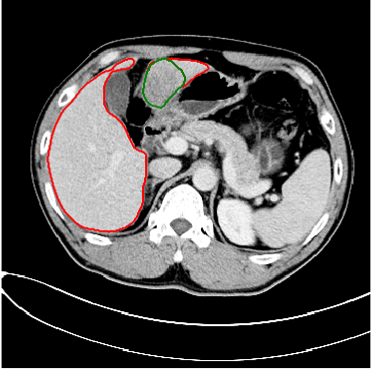

本次肝脏分割挑战赛的难点在于,相比于正常的器官,肿瘤没有固定的形状、大小和纹理,因此CT图像中肝脏肿瘤的分割极具挑战性。对此,沈超敏团队精心设计了数据预处理和3D神经网络的自动分割方法,使得肝脏及肝脏内的肿瘤均达到理想的精度。下面两图是肝脏与肿瘤的分割效果图,红色线段为肝脏区域边缘、绿色为肿瘤区域边缘。

图1 图2